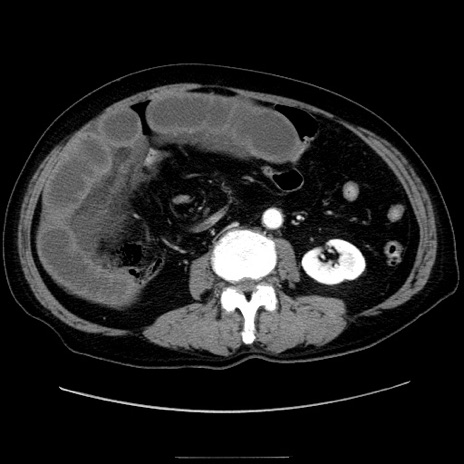

症例30(横断像)

【症例】80歳代男性

【主訴】臍周囲痛

【現病歴】約6時間前から臍下部痛が出現。次第に腹部膨隆・背部痛も生じてきたため来院。背部痛の場所は変化しない。

【身体所見】意識清明、BT 36.3℃、BP  131/87mmHg、P 87bpm、SpO2 100%(RA)、臍周囲自発痛・圧痛あり、反跳痛なし、自発痛部位に一致して板状硬あり、腹部膨隆、腸雑音減弱、CVA tenderness両側陰性。

【データ】WBC 19600、CRP 0.33